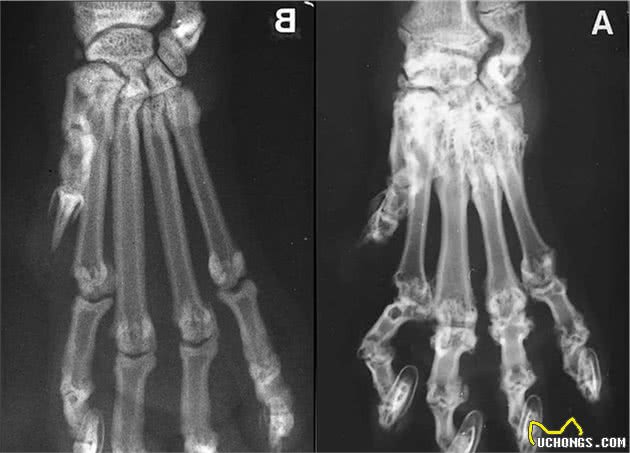

大家应该都听说过折耳猫的先天性遗传病-软骨骨质化发育异常。

1、发病后因为痛疼,会造成猫咪后腿不肯行走,两后腿更替坡行。也是有的猫在发病前期行为层面不受影响,但会发生小尾巴肌肉僵硬、不可以随意晃动。

2、猫咪的后腿过短,发现异常弯折,乃至有硬块等增微生物。

3、四肢关节肿胀,脚趾粗肿,灵活度下降,触摸有疼痛感。

最让人痛心的是,到现在为止,这类病症不可以防止、治不好,唯一能做的仅仅协助猫咪缓解楚痛及缓减恶变速率。当病情严重下去,人体骨骼变病的状况渐渐地扩散至脊柱,造成折耳猫偏瘫,导致巨大的痛苦。

但是如果已经买了一只折耳猫,如果你爱它,最最要紧的,带它去做X光检查。

要注意的是,X光检查只能证明到做检查为止没有发病,并不是永不发病,所以要定期体检。